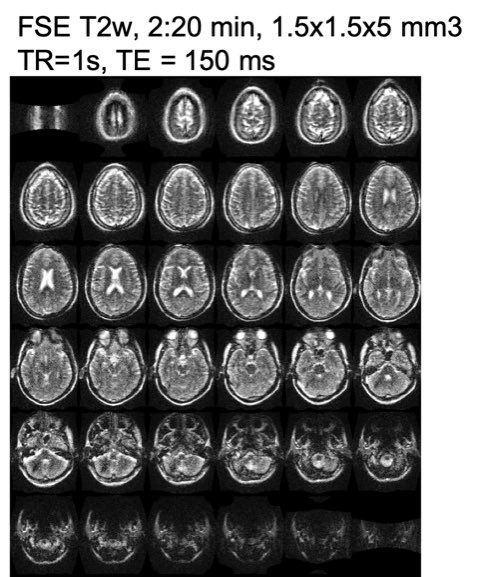

When you need to do an #MRI scan. At the bedside of your patient. In 2 minutes. From your #iPAD. #POCMRI. Thanks for taking care of those we love. #Healthcare@HyperfineR⁩ ⁦@PennMedicine⁩ ⁦@YaleMed⁩ ⁦@GatesFoundation⁩.